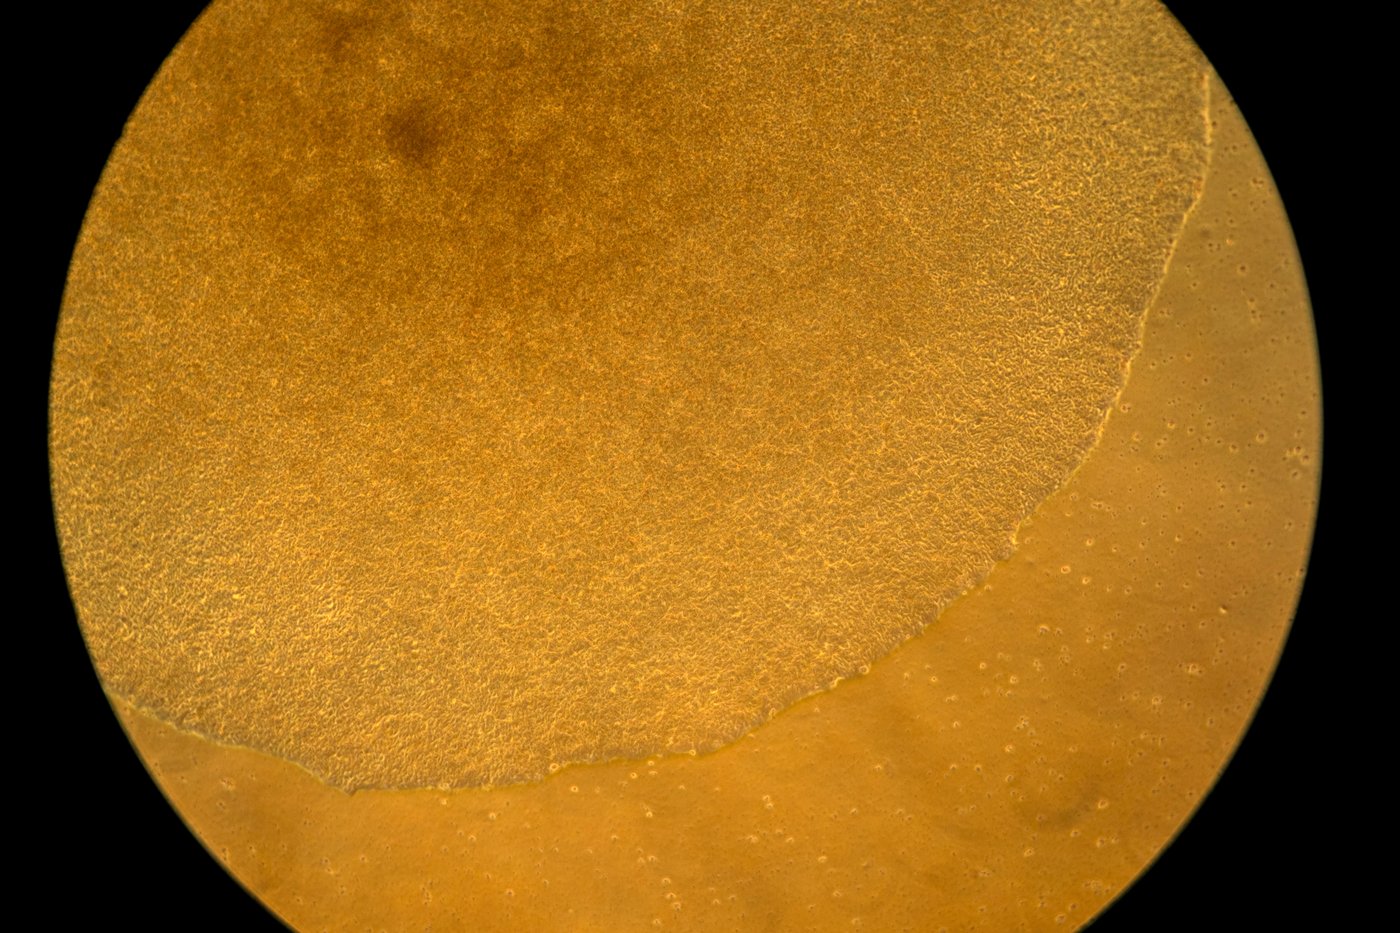

In Green’s lab, a computer screen shines with brightly colored dots that resemble a galaxy. It’s a biological map that shows insulin-producing cells in the pancreas of a mouse. Red marks rogue T cells that destroy insulin production. Yellow indicates those peacemaker regulatory T cells — and they’re outnumbered.

Green’s team aims to use that mRNA to instruct certain immune “generals” to curb the bad T cells and send in more peacemakers. They package the mRNA in biodegradable nanoparticles that can be injected like a drug. When the right immune cells get the messages, the hope is they’d “divide, divide, divide and make a whole army of healthy cells that then help treat the disease,” Green said.

The researchers will know it’s working if that galaxy-like map shows less red and more yellow. Studies in people are still a few years away.